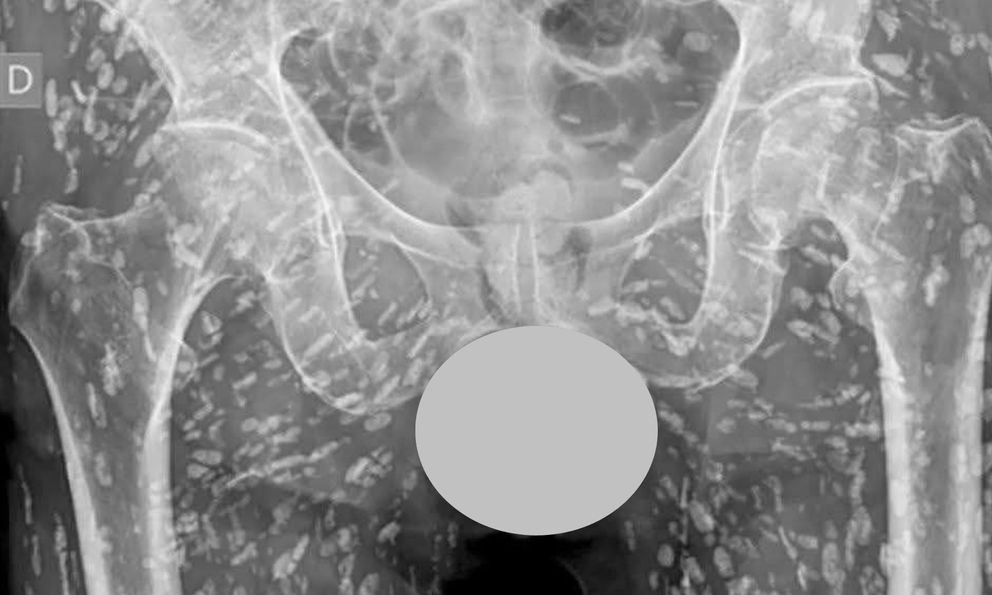

Được biết, bệnh nhân đến bệnh viện để kiểm tra tình trạng gãy xương hông. Tuy nhiên, trong quá trình chụp X-quang, các bác sĩ tình cờ phát hiện cơ thể bệnh nhân xuất hiện dày đặc các đốm trắng li ti – nghi là ký sinh trùng dưới da.

Nhìn vào hình ảnh phim chụp chi chít những đốm trắng nhỏ như hạt gạo chạy dọc cơ thể, nhiều người cho rằng đây là hậu quả của nhiễm ký sinh trùng lâu ngày. Một số người khác lại nghi ngờ đây là hình ảnh do AI tạo ra.

Bác sĩ Lê Văn Thiệu (Bệnh viện Bệnh Nhiệt đới Trung ương) khẳng định, hình ảnh X-quang lan truyền trên mạng xã hội là có thật, không phải do AI tạo ra. Theo bác sĩ, đây là trường hợp bệnh nhân bị nhiễm ký sinh trùng dưới da.

Nguyên nhân nhiễm ký sinh trùng chủ yếu là do thói quen ăn uống không an toàn, bao gồm: ăn thịt lợn sống, thịt tái, nem chạo, rau sống, gỏi cá – tôm,… Khi vô tình ăn phải thực phẩm nhiễm ký sinh trùng, ấu trùng sẽ đi vào cơ thể, sinh trưởng và phát triển. Ký sinh trùng sẽ hình thành các nang vôi hóa – hiện lên trên phim X-quang dưới dạng những đốm trắng li ti giống “hạt gạo”.

Đối với những trường hợp nhiễm nhiều ký sinh trùng như trong hình ảnh X-quang đang lan truyền, bác sĩ Thiệu nhấn mạnh cần đặc biệt thận trọng khi điều trị. Trước khi tiến hành tẩy ký sinh trùng, bệnh nhân cần được dùng corticoid dự phòng để tránh tình trạng sốc phản vệ do ký sinh trùng chết hàng loạt, giải phóng độc tố vào cơ thể.